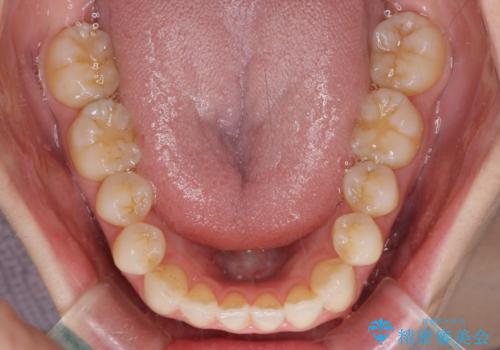

- 前歯の開咬を気にして来院された患者様です。

開咬の治療は、前歯を閉じるように動かすとともに、上下臼歯を圧下(骨内にめり込ませる)させることで進めて行きます。

インビザラインは臼歯の圧下を効果的に行えるため、インビザラインを用いて矯正治療を行うこととしました。